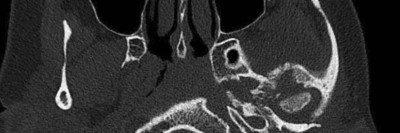

Was löst hier eine schwere Kiefergelenkzerstörung aus?

Weil die Schmerzen im linken Unterkiefer immer schlimmer werden, kommt die 26-jährige Patientin in die LMU-Klinik. Bereits seit fünf Jahren leidet sie unter wiederkehrenden Schmerzen im Unterkiefer. Anamnestisch hat alles angefangen mit einer Otitis media acuta.

Aufbau bei einer endoskopische Mittelohrchirurgie/© Mir-Salim P., Berlin, In-Ear-Kophörer/© diy13 / Stock.adobe.com (Symbolbild mit Fotomodell), CT des Felsenbeins bei Osteomyelitis der Schädelbasis/© Dewenter I.. et al. doi.org/10.1007/s00106-025-01649-6 unter CC-BY 4.0, Mikrobiom auf der Haut am Finger/© STEVE GSCHMEISSNER/SCIENCE PHOTO LIBRARY /Getty images / iStock, Otitis externa/© Dr. P. Marazzi / Science Photo Library (Symbolbild), Mann hält sich eine Hand ans Ohr/© herlanzer / stock.adobe.com (Symbolbild mit Fotomodell), Älterer Mann legt ein Hörgerät an/© VioletaStoimenova / Getty Images / iStock (Symbolbild mit Fotomodell), Kleinkind mit Cochleaimplantat/© satura86 / Getty Images / iStock (Symbolbild mit Fotomodell), Älterer Mann fasst sich ans Ohr/© Nes / Getty Images / iStock (Symbolbild mit Fotomodell), Ein Arzt bereitet das Hörscreening bei einer Frau vor/© kaisersosa67 / Getty Images / iStock (Symbolbild mit Fotomodell), Otoskopie bei einem jungen Kind/© SolStock / Getty Images / iStock (Symbolbild mit Fotomodellen), Hörgerät im Ohr einer älteren Person /© edwardolive / stock.adobe.com (Symbolbild mit Fotmodell), Frau mit schmerzverzerrtem Gesicht in Wohnzimmer/© fizkes / stock.adobe.com (Symbolbild mit Fotomodell), Mann erleidet Schwindel/© Tunatura / Getty Images / iStock (Symbolbild mit Fotomodell), Frau mit Kopfschmerzen/© MaximFesenko / Getty Images / iStock (Symbolbild mit Fotomodell), Eine ältere Frau riecht an einem Basilikumblatt/© Halfpoint / Stock.adobe.com (Symbolbild mit Fotomodell), Otoskopie in der Praxis/© RomanR / stock.adobe.com (Symbolbild mit Fotomodell), Person hält Medikamente/© fizkes / Stock.adobe.com (Symbolbild mit Fotomodell), Titel/© J. Hornung, Erlangen, Cholesterolgranulom im MRT/© Frederik F/ all rights reserved Springer Medizin Verlag GmbH, Tampanometrie bei einem Kind/© peakSTOCK / Getty Images / iStock (Symbolbild mit Fotomodell), Kleine Saktosalpinx rechts /© Universitätsklinikum Carl Gustav Carus, Dresden, Tympanometrie bei einer Frau/© Viacheslav Yakobchuk (Symbolbild mit Fotomodell), Hörgerät Modell/© Kaulitz S et al. / all rights reserved Springer Medizin Verlag GmbH, Eine Lehrende Person unterhält sich mit einem Kind mit Cochlea-Implantat/© vgajic / Getty Images / iStock (Symbolbild mit Fotomodell), Mann mit Zeichen einer Schwerhörigkeit/© Rido / stock.adobe.com, Computertomographie Felsenbein links /© Marti S et al. doi.org/10.1007/s00106-025-01602-7 unter CC-BY 4.0, Neugeborenen-Hörscreening/© isayildiz / Getty Images / iStock (Symbolbild mit Fotomodell), Eine Frau steckt sich die Finger in die Ohren zum Schutz vor Lärm/© apomares / Getty Images / iStock (Symbolbild mit Fotomodell), Atemwegsinfektionen/© (M) RFBSIP / stock.adobe.com / stock.adobe.com (Symbolbild mit Fotomodellen), Search Icon, HNO-Untersuchung beim Jungen/© adamkaz / Getty Images / iStock (Symbolbild mit Fotomodellen), Infusion/© georgeoprea9 / Getty Images / iStock